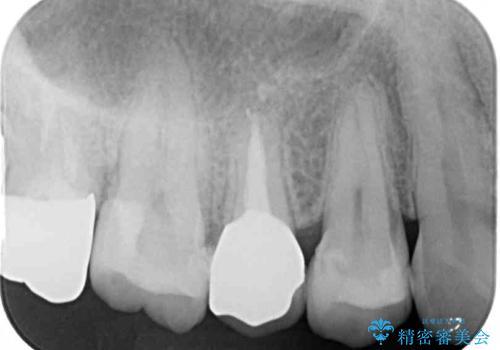

右上の歯は噛んだときに何カ所か痛みを感じるとのことで、診査したところ第二小臼歯が患歯と疑われました。

患者様は他の歯にも痛みを感じるとおっしゃっていましたが、そのような所見が認められなかったため、まずは第二小臼歯を処置し、その痛みが引いた後に再診査することとしました。

右上の歯は、第二小臼歯の初回処置後に痛みを感じなくなったため、他の歯については問題なしと診断しました。